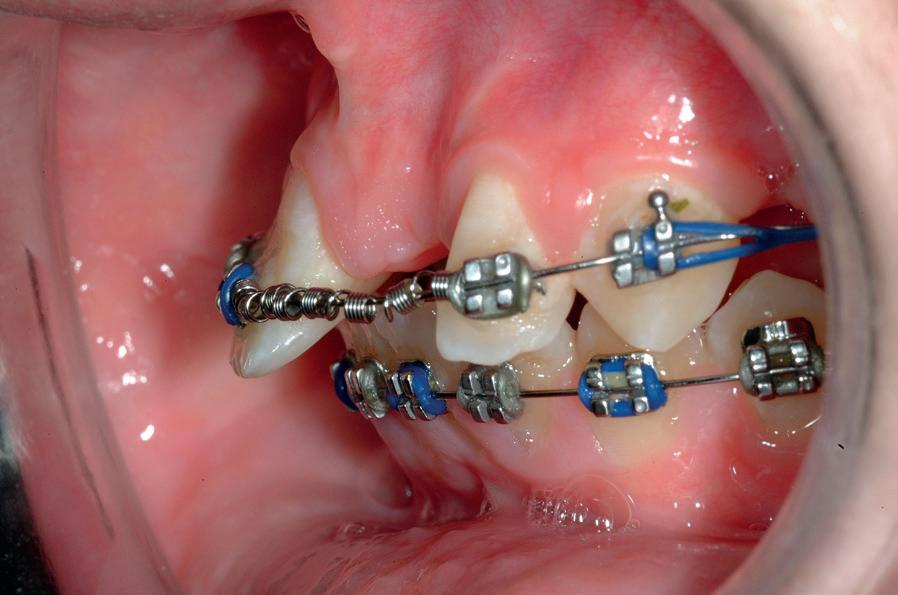

RECONFIGURAREA suportului osos implantar. În cazul prezentat, după ani de terapie ortodontică incorect executată, dezvoltarea dentară a pacientului a complicat obținerea unui zâmbet estetic. S-a reanalizat și s-a optat pentru abordare interdisciplinară care cuprinde chirurgia parodontală, un al doilea tratament

ortodontic și protetica pentru a oferi îngrijirea comprehensivă.